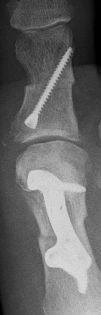

Roentgenbild  Roentgenbild von oben und von der Seite